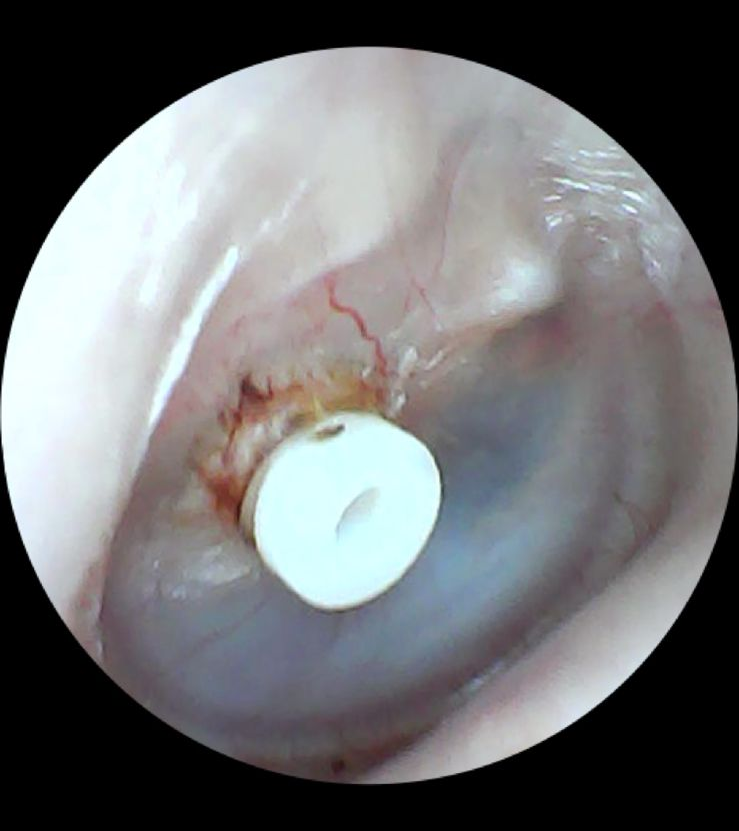

O tubinho de ventilação é um pequeno cilindro, semelhante a um carretel, geralmente de plástico, inserido no tímpano por meio de cirurgia. Ele cria uma abertura que permite a passagem de ar entre o meato acústico externo e a orelha média, equilibrando a pressão interna e evitando o acúmulo de secreções.

O procedimento, chamado timpanotomia, é geralmente feito sob anestesia geral. O médico realiza uma pequena incisão no tímpano, drena o líquido acumulado e insere o tubinho. O processo é rápido, dura poucos minutos e, na maioria dos casos, o paciente recebe alta no mesmo dia.

Os tubos de ventilação se diferenciam principalmente pelo tempo que permanecem no tímpano, sendo classificados como curta duração ou longa duração: